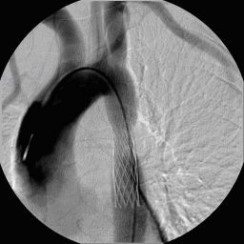

Vor perkutaner transluminaler Angioplastie (PTA) der Unterschenkelgefäße

(Bild 3 von 4)